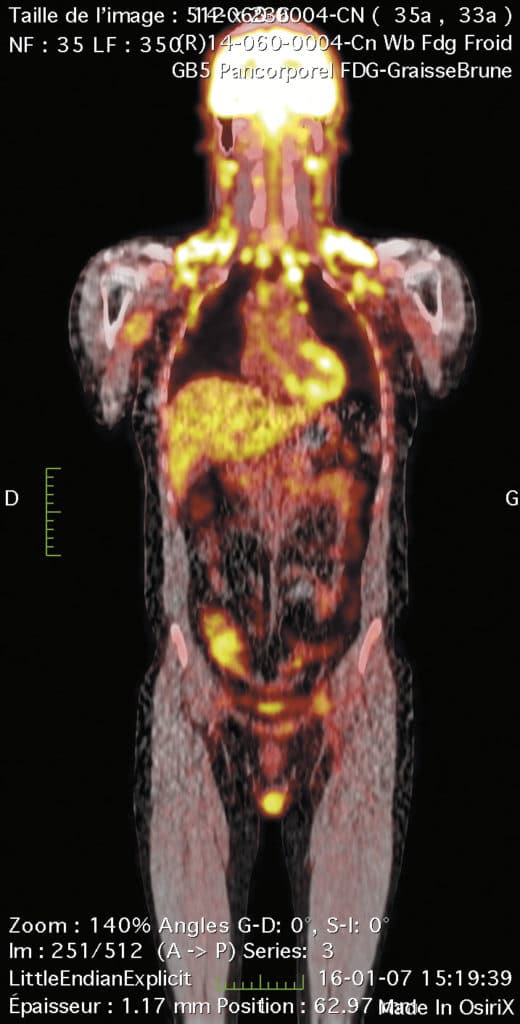

然而,Carpentier教授使用非侵入性PET(正电子发射断层摄影术)成像的方法克服了这些局限性。PET是一种灵敏的成像技术,可以检测微小(皮摩尔)示踪剂浓度。Carpentier教授进行了一项研究,健康受试者口服放射性标记示踪剂FTHA (14-R, s -f -氟-6-硫-十七烷酸),这是一种长链脂肪酸类似物。随后进行了6个多小时的连续全身PET采集。在此期间,所有示踪剂的运动被记录为三维图像,以突出全身示踪剂的划分。从本质上说,这使得DFA在不同组织和器官中的脂肪储存得以测量。结果表明,健康男性肝脏和心脏的DFA含量较高。然而,骨骼肌和皮下脂肪组织储存的DFA含量相对较低。

Carpentier教授还研究了DFA在棕色脂肪组织(BAT)中的分配。BAT的功能是通过生热调节体温——通过氧化脂肪储存产生热量来提高体温。受试者口服FTHA并暴露于18°C的低温环境中。PET成像结果证实BAT在冷曝光时确实摄取DFA。然而,BAT组织每体积的DFA分配比肝脏低83%,比心脏低55%,仅占全身DFA清除的0.3%。